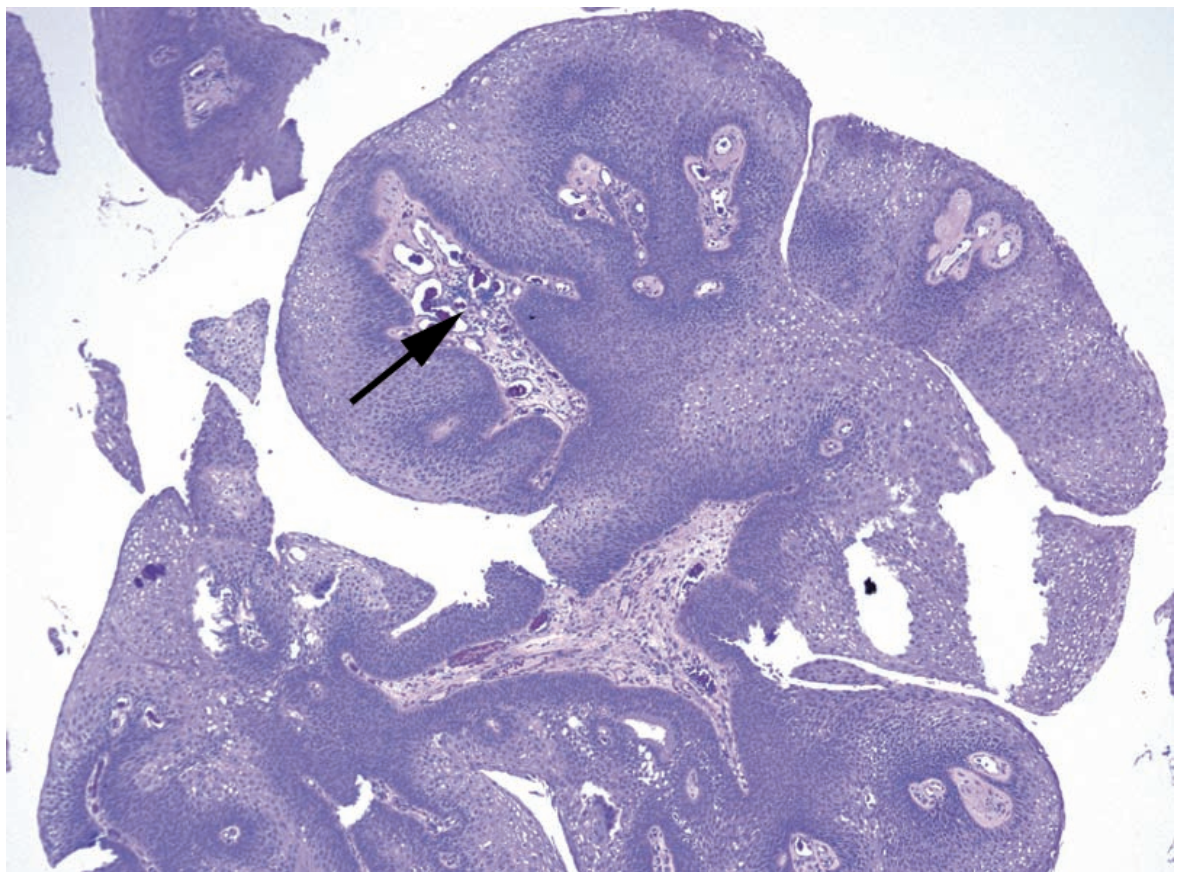

Q

A

Pseudoepitheliomatous hyperplasia

Arrow: Strands of epithelium pulled into the dermis or LP without keratinization or invasion.